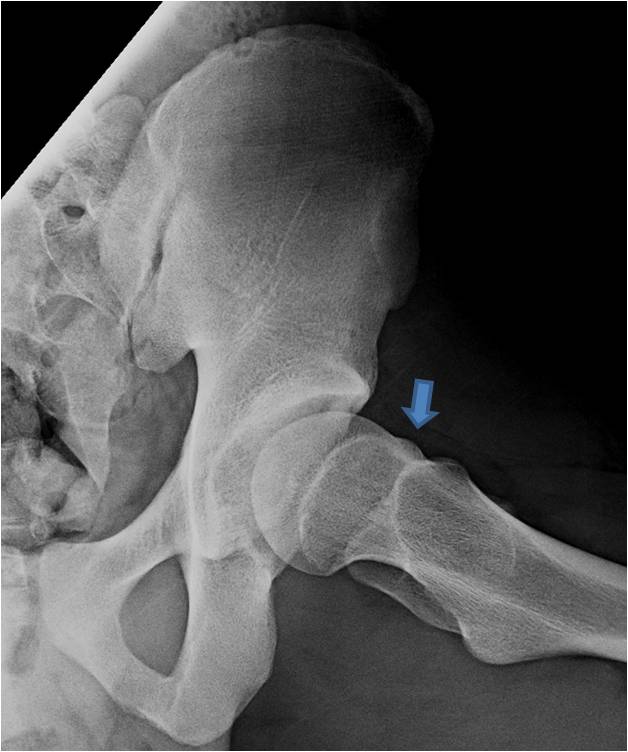

A while back I consulted with the Foundation for Goalie Research and Education on their Hockey Hip Injury Prevention Project. FGRE is an organization that I was introduced to by Molly Schaus, long-time member of USA Hockey’s Women’s National Team. The goal for this particular project was to help create a simple, equipment-free warm-up that […]